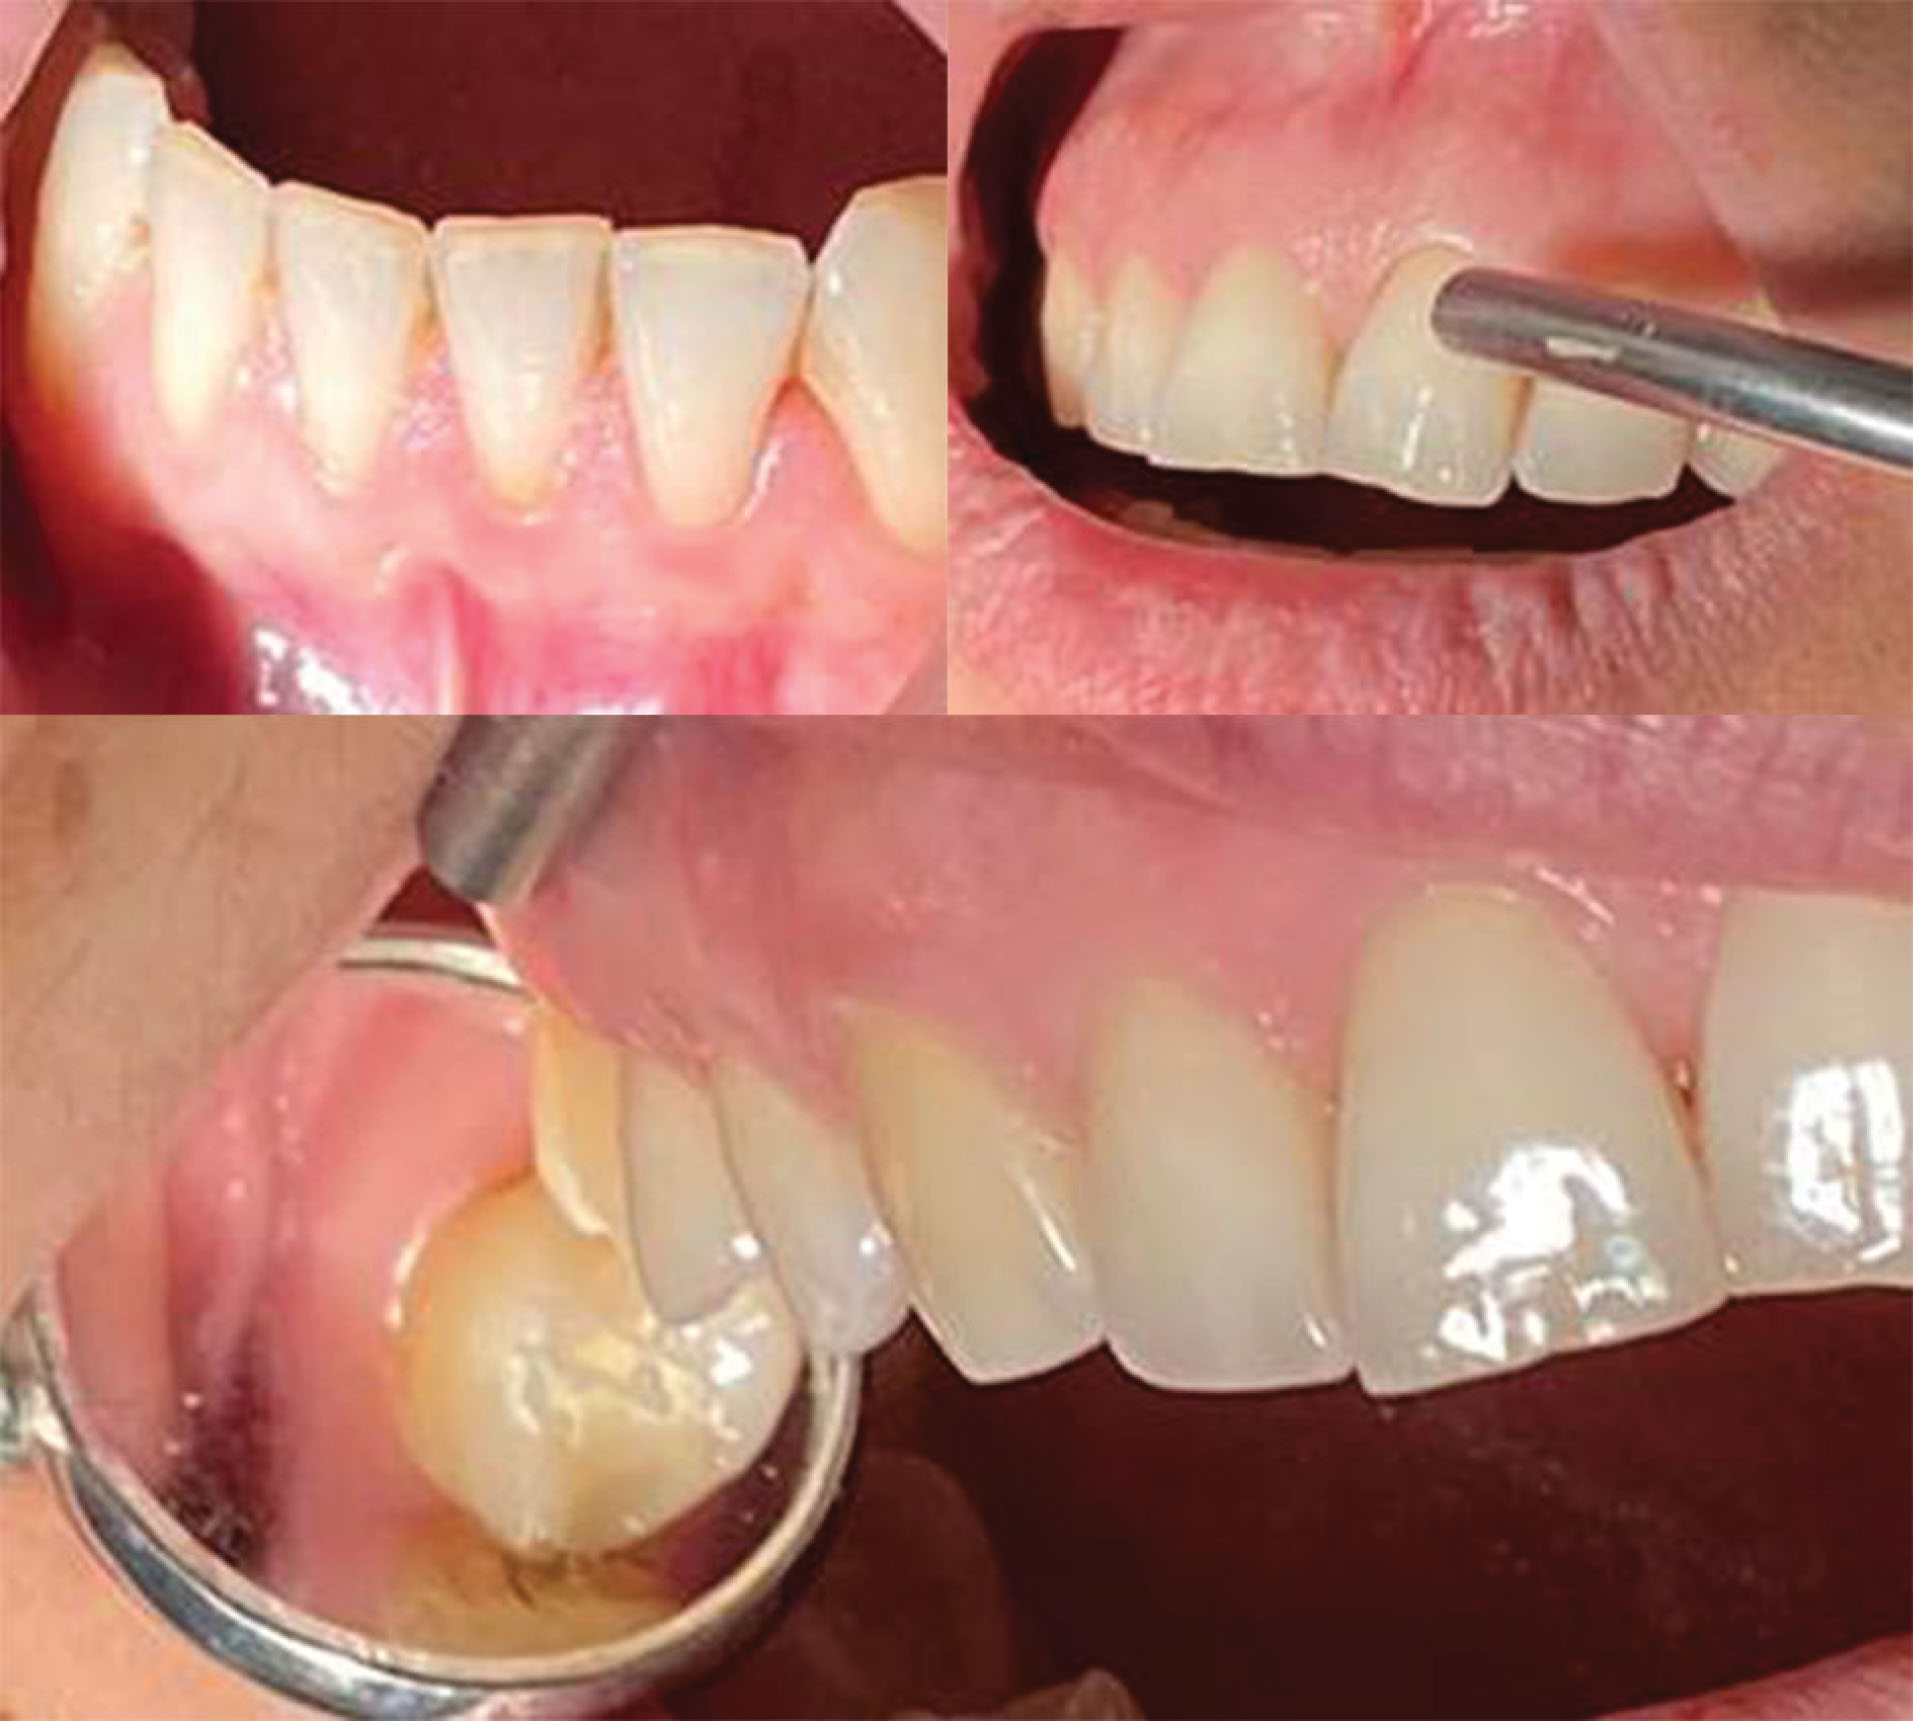

japid-13-22-g003

Figure 3. Patients with periodontitis, age 33 years, where there is an almost total absence of bacterial plaque, even in the maxillary molars. The pink color of the gingiva and orange peel is a clinical sign of gingival health.